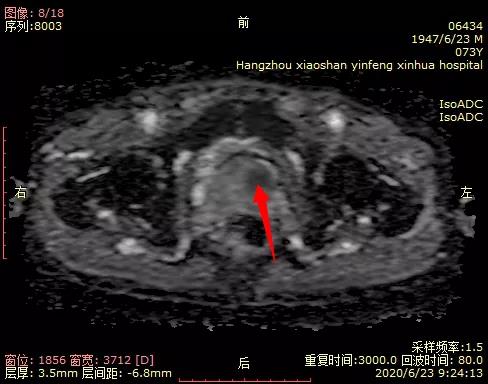

05 磁共振新技术的应用 前列腺弥散加权成像(DWI)对前列腺癌定性诊断有重要意义;可以作为PSA值异常后的常规筛查。